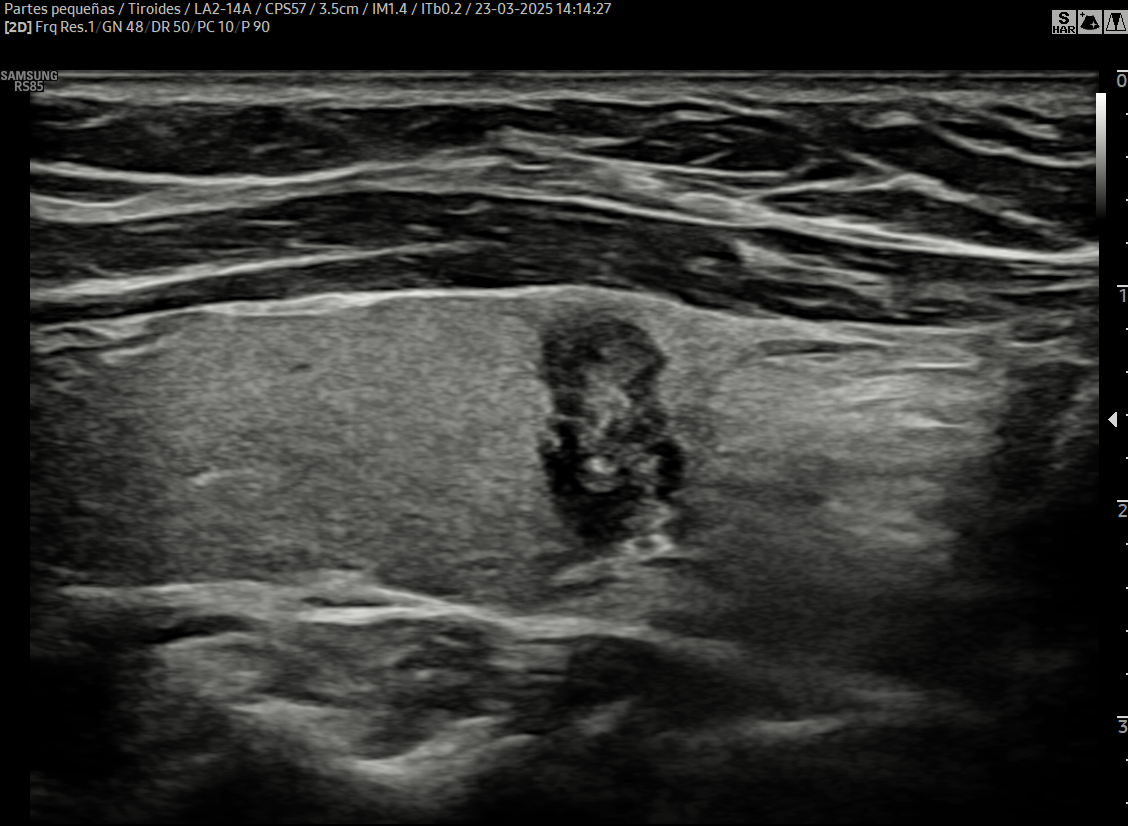

Diagnóstico preciso de nódulos tiroideos

La segunda opinión en ecografía de tiroides es una evaluación especializada que permite confirmar, aclarar o complementar un diagnóstico previo de nódulos tiroideos o enfermedades tiroideas.

Dado que la interpretación de la ecografía tiroidea depende en gran medida de la experiencia del operador, una segunda opinión realizada por un especialista permite obtener una evaluación más precisa, objetiva y confiable, especialmente en casos complejos o dudosos.

En Diagnoimagen - Dr. Hubertino Díaz, la segunda opinión se realiza mediante un enfoque de ecografía multiparamétrica avanzada, que incluye:

🔹Revisión detallada de estudios previos

🔹Ecografía de alta resolución

🔹Doppler tiroideo avanzado

🔹Elastografía de nódulos tiroideos

🔹Evaluación ganglionar cervical (mapeo ganglionar)

Este enfoque permite una caracterización completa de los nódulos tiroideos, mejorando la precisión diagnóstica.